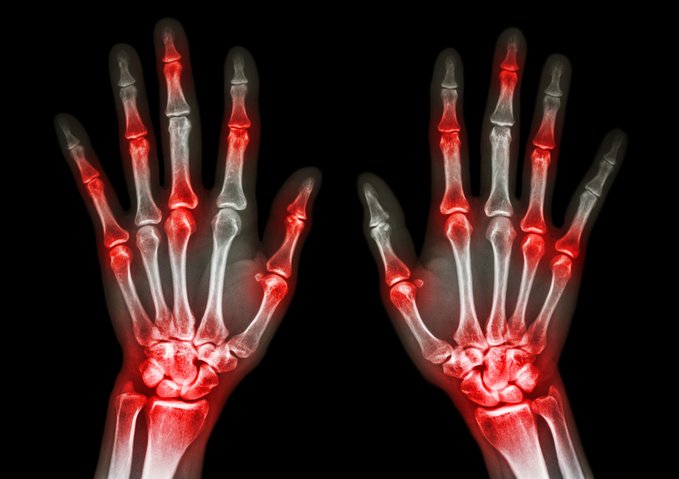

Suspensión de adalimumab en la uveítis asociada a artritis idiopática juvenil: un ensayo clínico aleatorizado

La interrupción del tratamiento con adalimumab provocó tasas más altas de recurrencia de uveítis, artritis o ambas en pacientes con uveítis asociada a artritis idiopática juvenil previamente controlada. Sin embargo, todos los pacientes que fracasaron en el tratamiento recuperaron con éxito el control de la inflamación al final del período de estudio de 48 semanas después de reiniciar el tratamiento con adalimumab. The Lancet, 25 de enero de 2025.